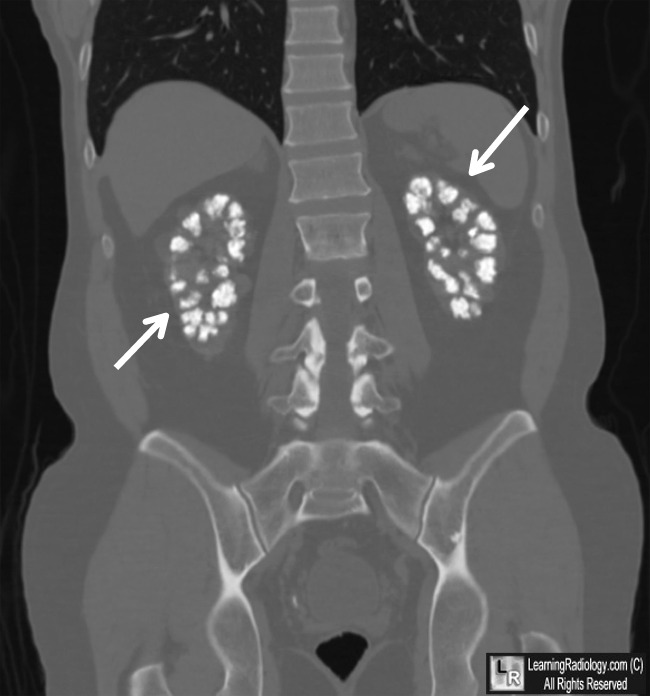

From www.learningradiology.com

LearningRadiology Medullary Sponge Kidney Stones medullary sponge kidney is a benign congenital abnormality that was first described in 1939. medullary sponge kidney (msk) is a birth defect of the tubules inside the kidneys. Anatomically it is characterized by cystic. Problems caused by msk include. medullary sponge kidney (msk) is a rare, developmental abnormality characterised by ectatic (dilatory) or. the first sign. Medullary Sponge Kidney Stones.

LearningRadiology Medullary Sponge Kidney Stones Utis and kidney stones share many of the same signs. medullary sponge kidney (msk) is a birth defect of the tubules inside the kidneys. Problems caused by msk include. medullary sponge kidney is a benign congenital abnormality that was first described in 1939. Anatomically it is characterized by cystic. the first sign that a person has medullary. Medullary Sponge Kidney Stones.

LearningRadiology Medullary Sponge Kidney Stones medullary sponge kidney is a benign congenital abnormality that was first described in 1939. medullary sponge kidney (msk) is a rare congenital disorder where small cysts form in the kidneys, possibly. Anatomically it is characterized by cystic. medullary sponge kidney (msk) is a rare, developmental abnormality characterised by ectatic (dilatory) or. the first sign that a. Medullary Sponge Kidney Stones.